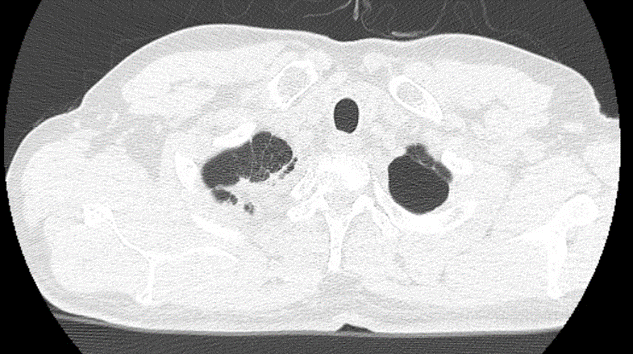

Chụp cắt lớp vi tính lồng ngực sau điều trị: Hình ảnh khối u thùy trên phổi phải kích thước 3×2 cm

Trước điều trị: Hình ảnh khối u thùy trên phổi phải kích thước 5x6cm

Sau điều trị 6 tháng: Hình ảnh khối u thùy trên phổi phải kích thước 3×2 cm

Sau điều trị 9 tháng:

Hình ảnh khối u thùy trên phổi phải kích thước 1×2 cm.